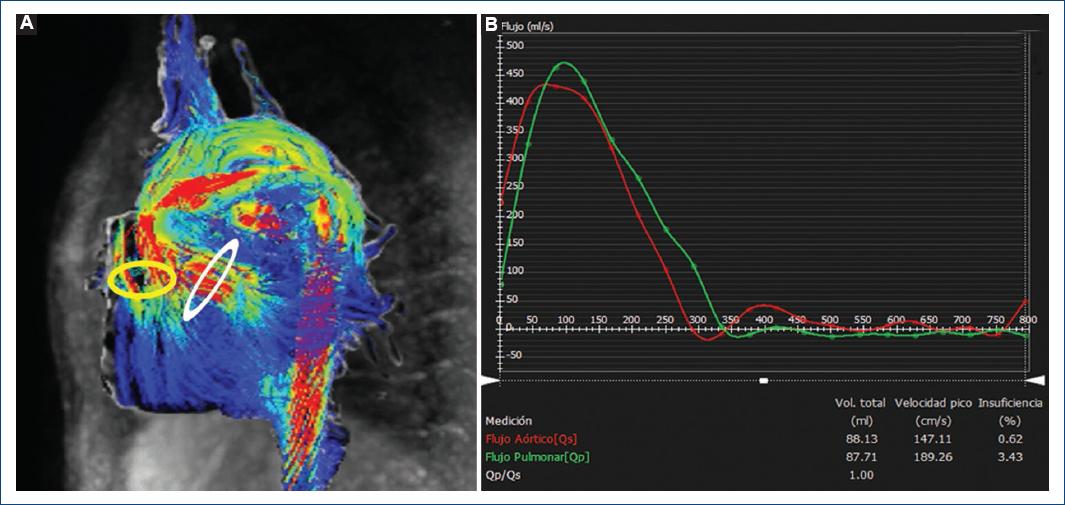

En el ejemplo 1 se muestra el estudio de un paciente con comunicación interauricular ostium secundum que es el más frecuente (70% de todas las comunicaciones interauriculares). Se presenta en la zona central del tabique auricular, lo que tiene como consecuencia de forma inicial un cortocircuito izquierda-derecha, también conocido como «derivación», a través de la comunicación interauricular, lo que condiciona una sobrecarga de volumen en las cavidades cardiacas derechas e hiperflujo pulmonar, pudiendo cursar con hipertensión pulmonar, arritmias auriculares e insuficiencia cardiaca9,10. En este caso, en las secuencias de flujo 4D fue posible ubicarnos directamente sobre el defecto interauricular de forma perpendicular sobre el flujo de comunicación interauricular, permitiendo analizar su localización y morfología a nivel del septo interauricular, llevar a cabo las mediciones necesarias (diámetros y área) en la fase del ciclo cardiaco y, ciertamente, la medición directa del flujo (Fig. 1). Así mismo, mediante software de análisis avanzado fue ejecutable la activación de vectores y uso de streamlines y pathlines que nos permitieron identificar claramente de forma visual la dirección del flujo, tan importante en este tipo de patología cardiaca. Al mismo tiempo, la secuencia de flujo 4D nos permitió la cuantificación del Qp:Qs, el flujo sistémico (Qs) y el flujo pulmonar (Qp) en cualquier nivel deseado; de esta forma es posible una excelente valoración interna de las diversas mediciones que llevan a una mayor congruencia del análisis y los posteriores resultados (Fig. 2).

Figura 2 A: resonancia magnética cardiaca en secuencia de flujo 4D identificando el flujo aórtico (punta de flecha), el flujo pulmonar (flecha) y la comunicación interauricular (círculo). B: tabla de cuantificación de flujo de Qp/Qs, a nivel aórtico, pulmonar y en la comunicación interauricular.